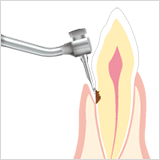

Til rensning af rodkanal

Diamantcoatet / Til udvidelse af rodkanal

Rensning af rodkanal